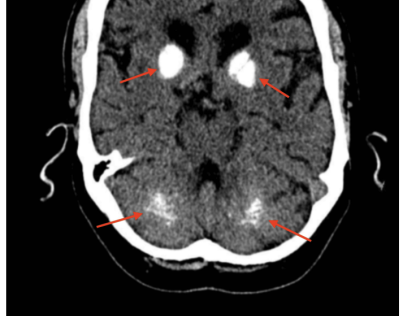

Fahr’s Syndrome Secondary to Hypoparathyroidism Presenting With Neurological and Cardiac Manifestations